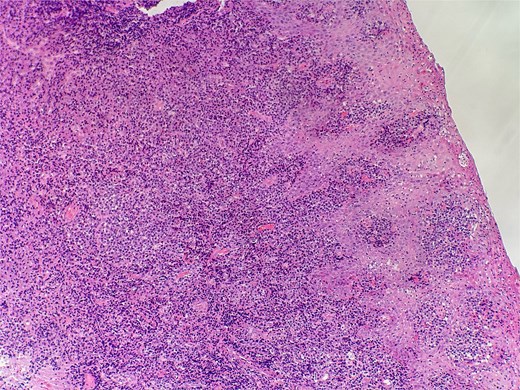

On clinical examination, harsh stridor with increased work of breathing was noted. Flexible nasoendoscopy demonstrated generalized supraglottic oedema with impending upper airway obstruction. Intravenous dexamethasone was commenced. A surgical tracheostomy with laryngeal biopsies under general anaesthetic was carried out. Histological examination (Figs 1 and 2) demonstrated hyperplastic, hyperkeratotic squamous mucosa with reactive atypia and an underlying dense polyclonal plasmocytic inflammatory infiltrate. No granulomata, prominent eosinophils, or stigmata of vasculitis were seen. Connective tissue disease screening demonstrated normal antinuclear antibody levels with positive perinuclear anti-neutrophil cytoplasmic antibodies. Anti-proteinase 3 levels returned as 3.7 IU/ml (range 0–1.9), while antimyeloperoxidase levels were normal. Rheumatology was consulted, and a provisional diagnosis of PCM was made. Serial laryngoscopy demonstrated resolution of the oedema, with the supraglottis regaining a normal appearance despite gradual tapering of the intravenous dexamethasone. A tracheostomy capping trial was successful. The patient was decannulated uneventfully and discharged on oral prednisolone. Three months later, he was maintained on 5 mg prednisolone—attempts to taper any further caused symptoms recurrence. Outpatient referral was made to Rheumatology for medical management with steroid-sparing therapy. Unfortunately, the patient was lost to follow-up due to failure to attend for outpatient review.

Slide from epiglottis specimen at index presentation showing squamous mucosa and underlying polyclonal plasmocytic infiltrate.